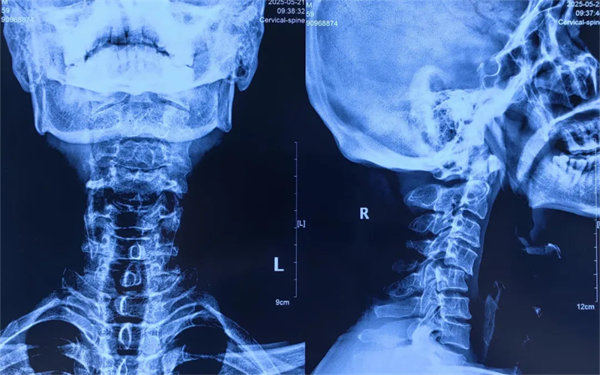

近日,我院骨四科團隊成功為一名因摔傷導致頸4/5椎骨折脫位、頸脊髓損傷的60歲男性患者實施前路切開復位椎間盤切除減壓植骨椎間融合術(ACDF),幫助患者擺脫病痛,重新回歸正常生活。這一病例也為公眾敲響警鐘:看似常見的頸椎損傷,若處理不當可能引發(fā)嚴重后果,科學救治刻不容緩。

術前

患者受傷后曾在外院接受保守治療,但肢體麻木癥狀持續(xù)存在。轉入我院時,頸椎CT及MRI顯示:頸4/5椎骨折脫位,脊髓受壓明顯,若不手術治療,可能面臨永久性神經功能障礙。我院骨四科團隊,制定了前路ACDF手術方案:通過頸前側入路,切開復位、切除椎間盤,解除脊髓壓迫,同時植入融合器、鈦板固定,重建頸椎正常序列及穩(wěn)定性。術后患者麻木感消失,復查顯示頸椎序列恢復良好,目前已康復出院。